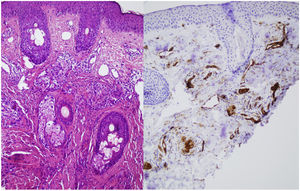

A skin biopsy was performed on one of the malar lesions and revealed dilated capillaries and venules in the superficial dermis, occasionally occupied by a proliferation of fusiform cells without atypia and with clear cytoplasms. No significant inflammatory infiltrates, bleeding or involvement of the interface. Immune staining showed these cells to be endothelial, predominantly positive for CD31 and negative for D2-40 (Fig. 2). This led to a diagnosis of reactive angioendotheliomatosis in a context of primary antiphospholipid syndrome.

Histopathology reveals poorly circumscribed, dilated grouped capillaries with endothelial cells without atypia in the dermis and the subcutaneous cellular tissue. The architecture of the CD31+ intravascular proliferation may take on a lobular or diffuse glomerular pattern. These structures are negative for histiocyte markers (CD68) and lymphatic markers (podoplanin or D2-40). Fibrin thrombi or microthrombi are frequently found. The presence of an accompanying lymphocytic infiltrate varies.2,3 The histiologic differential diagnosis includes malignant angioendotheliomatosis and intravascular lymphoma. Histology and immune staining are key to diagnosing this entity.